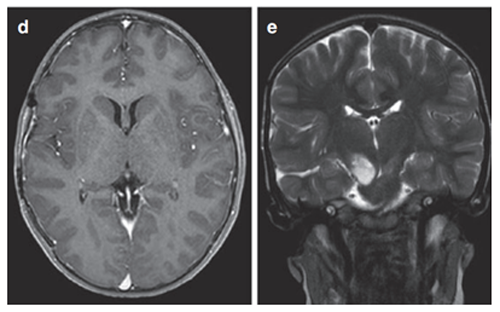

患者是一名6岁男童,症状为头痛、间歇性左上肢震颤。MRI(FLAIR序列)显示一个两侧丘脑肿瘤,右比左大,尾状核的右头部也参与其中。脑室轻度增大,膈膜水肿,肿瘤内部囊肿。因此,Rutka教授为其先行左额部内窥镜活检和鼻中隔造瘘术,再行左枕脑室-腹腔分流术。

(图8)

组织病理诊断为WHO III级间变性星形细胞瘤,H3K27M、p53、BRAF V600E突变免疫阴性。MIB-1增殖指数为40%。至此,Rutka教授为患儿制定了周密的综合治疗方案,患儿开始同时接受替莫唑胺(TMZ)和放射治疗(59.4 Gy),并接受累计剂量为200 mg/m2的12个周期的持续替莫唑胺治疗。该男孩在确诊后15个月放射学表现稳定,症状也得以缓解,生活质量有所提升。